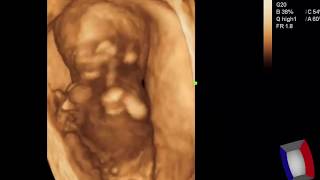

Case 373 2D 3D 4D Fetal Phocomelia Meromelia

631

3:21